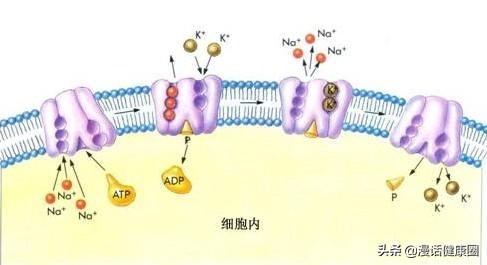

La physique au niveau de l'enseignement secondaire nous apprend que la production de courant électrique est essentiellement un flux d'électrons (charges positives) dans une direction. Dans chaque cellule du corps humain, c'est le mouvement cyclique constant des ions sodium (charge positive) et potassium (charge positive) qui génère la faible bioélectricité à l'origine de toutes les fonctions de l'organisme. Le mécanisme spécifique est le suivant : la cellule consomme de l'énergie, trois ions sodium sont pompés hors de la cellule et deux ions potassium sont pompés dans la cellule, l'équivalent d'une charge positive de la cellule vers l'extérieur de la cellule, la formation d'une différence de potentiel entre l'intérieur et l'extérieur de la cellule, résultant en une bioélectricité, qui est connue des étudiants en médecine sous le nom de "pompe sodium-potassium" et de "potentiel de repos cellulaire". C'est ce que les étudiants en médecine connaissent sous le nom de "pompe sodium-potassium" et de "potentiel de repos cellulaire", qui sont tous deux les pierres angulaires de la vie.

Quatre-vingt-dix-huit pour cent du potassium présent dans notre corps se trouve à l'intérieur des cellules, tandis que le reste se trouve dans les fluides extracellulaires, y compris le sang.钠钾泵à maintenir !

Il s'agit d'une question très complexephysiologiqueLe problème, qui est difficile à expliquer, peut être compris simplement comme le fait d'avoir une telle structure pour maintenir les ions sodium et potassium normaux à l'intérieur et à l'extérieur de nos cellulesdifférence de concentration。

celui-ciLe bon fonctionnement de la pompe sodium-potassium est très important pour le fonctionnement de nos nerfs et de nos muscles.En cas de changements anormaux dans les concentrations intracellulaires et extracellulaires de sodium et d'ions potassium, il est possible d'affecter gravement le système nerveux central.Nerfs, musclesLa fonction de la

Le potassium est l'un des éléments importants du corps humain, il constitue avec le sodium la pompe sodium-potassium du transport cellulaire, qui contribue au transfert des substances à l'intérieur et à l'extérieur de la cellule. Le potassium est étroitement lié à la fonction physiologique normale des cellules, et une fois que les symptômes d'un faible taux de potassium apparaissent, cela affectera l'organisme de nombreuses façons, aujourd'hui, suivez la bande dessinée pour parler de si l'organisme est déficient en potassium, quels sont les symptômes qui seront stockés dans l'organisme ?

3) Le troisième rôle du potassium est de maintenir la conduction dans les cellules du muscle cardiaque. Nous savons que les battements du cœur dépendent du battement régulier des cardiomyocytes pour pouvoir pomper le sang normalement, et la conduction de ce signal dépend du transfert des ions potassium à l'intérieur et à l'extérieur des cellules pour qu'une conduction régulière se produise.la conduction normale des signaux électriques dans les cardiomyocytes.Il en résulte un dysfonctionnement des cardiomyocytes, qui peut être à l'origine dearythmieet d'autres symptômes typiques.